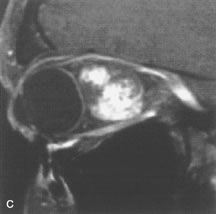

Application of a 90° RF pulse brings the excited nuclei into phase so that the net vector of their magnetic moments is directed perpendicular to the static magnetic field. Shortly thereafter, the magnetic moments of the nuclei spread out and point in different directions, leading to a loss of phase coherence and a resultant decay in signal intensity amplitude. The T2, or spin-spin relaxation time, is the rate of decrease in the signal of these excited nuclei as a result of the interaction and transfer of energy to unexcited adjacent nuclei. T2 ranges from a few milliseconds to a few hundred milliseconds and, for a given tissue, is always less than the Tl relaxation time. T2-weighted orbital images are easily recognized by a high-intensity signal from the vitreous (Fig. 9).5,8,16